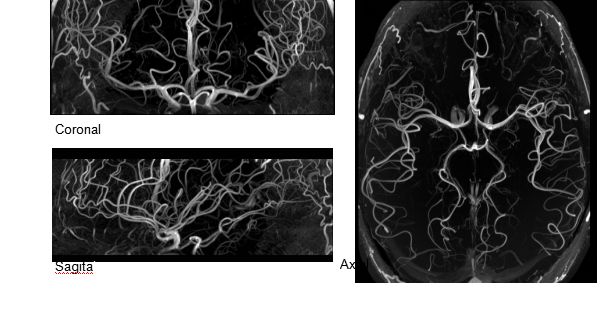

1毫米的各向同性分辨率DTI:神經(jīng)纖維束的交叉細(xì)節(jié)顯示

0.8毫米的各向同性分辨率:精確劃分灰質(zhì)和白質(zhì)

0.8毫米的各向同性分辨率:超精細(xì)的解剖細(xì)節(jié),例:小腦的精細(xì)結(jié)構(gòu)

超精細(xì)的解剖細(xì)節(jié):T2對(duì)比

0.17 x 0.17 x 0.8毫米分辨率超高。

(TOF)300微米的各向同性分辨率顯示最小的血管